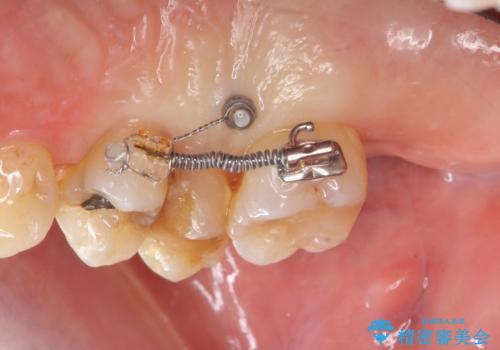

連結補綴について

特定の歯に強く力がかかりまた歯周病により臨床歯根が短くなっているような場合、歯の動揺を抑えるため連結補綴が検討されます。

歯の動揺が続くとより周囲の骨を失い最終的には歯を喪失してしまう可能性が高くなってしまうためです。

今回連結補綴を行うにあたり、歯周病の問題を解決するために再生療法・歯周ポケット除去手術を、またより歯の神経を保存し力に対抗できる環境を整えるために小矯正を行い精度の高いメタルボンドクラウンを製作することができました。